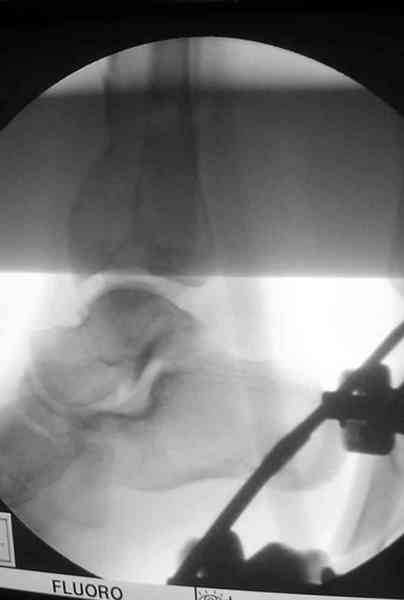

Открыто или закрыто - это уже зависит от опыта и

наличия материала. Минимальным аппаратом Илизарова или одним из Contoured Medial или Antero-Lateral Locking Plate из лимитирванного доступа не имеет значения, но самое главное необходимо добиться репозиции сустава.

Здесь выставлена пара случаев перелома пилона, оба

случая леченные этапным наружным фиксатором.

Второй случай фиксирован аппаратом Илизарова.